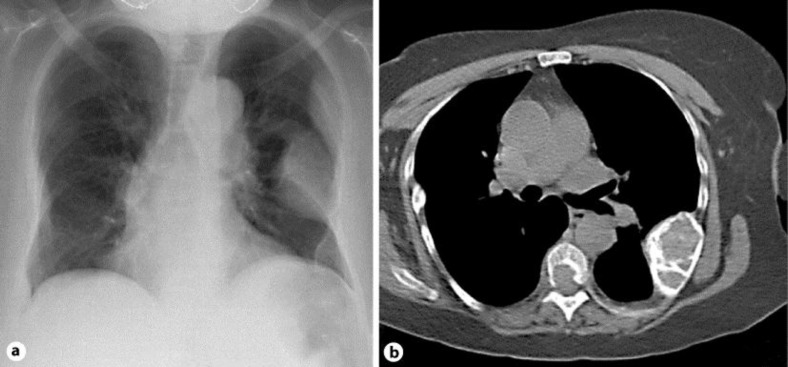

Pyogenic granuloma is a benign vascular tumor of the skin or mucosae usually observed after irritative processes. We report the case of a non-compliant hemodialysis patient with severe hyperparathyroidism who rapidly developed growing pyogenic granuloma of the distal part of the left thumb. This tumor mimicked sarcoma and caused recurrent bleeding during hemodialysis sessions. Hand radiograph revealed an osteolytic lesion compatible with a brown tumor. Among other brown tumors, several of those found in the ribs were responsible of a severe respiratory restrictive deficit. This report highlights the difficulty to choose the adequate treatment of severe hyperparathyroidism, and discusses the benefit/risk balance of performing parathyroidectomy.